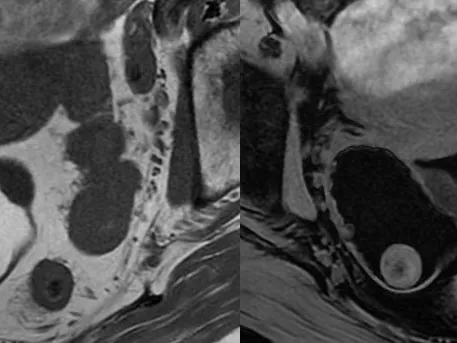

▶ Part 2 covers: MRI Adnexal Lesion Characterisation / Ovarian Cancer Staging / Chronic Pelvic Pain / Endometriosis / Acute Pelvic Pain / Imaging of Mesh Complications

- Lectures on reading female pelvic MRI for diagnosis of uterine anomalies, adnexal lesion characterisation, evaluation of acute and chronic pelvic pain, evaluation of uterine fibroids and staging and follow up of uterine malignancies